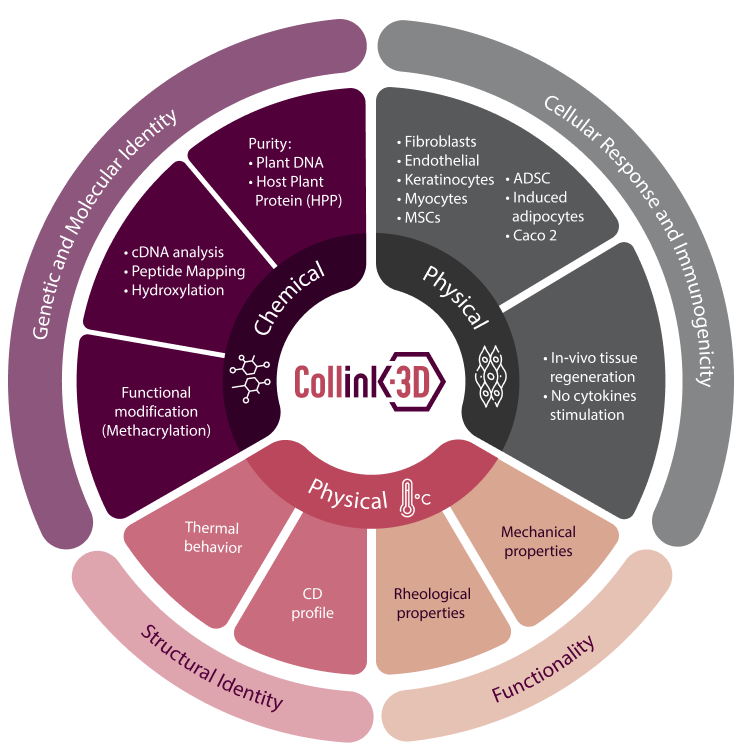

Collink.3D™ chemical, physical and

biological characterization

Extensive studies carried out to characterize the chemical, physical and

biological characteristics of Collink.3D™ confirmed its identity to human

type I collagen and its performance as a bioink.